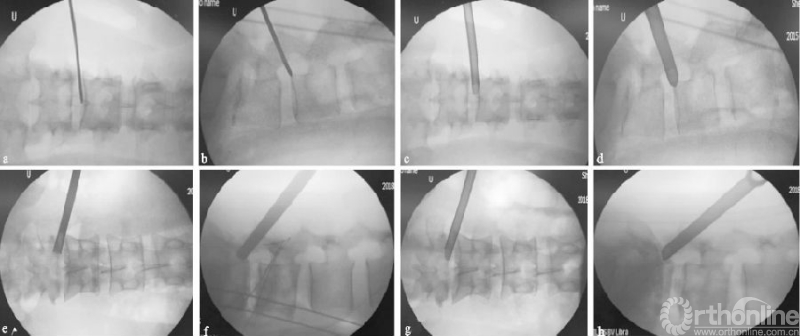

向上游离的腰椎间盘突出症由于没有上关节突的阻挡,一般通过水平穿刺或向上稍倾斜角度的穿刺,不需要行关节突成形,利用工作套管的活动度及带角度的髓核钳,可相对容易摘除椎间盘(见图4a-d);而对于向下游离的腰椎间盘突出症,要根据游离物的大小及方向,来行适当的关节突成形以扩大偏下方的椎间孔区,以顺利摘除椎间盘,减少残留可能(见图4e-h)。

游离型腰椎间盘突出症为椎间盘向上或向下脱垂,Fardon和Lee等[15-16]有详细的分型。在向下游离的突出中,有一个“隐蔽区”[17],该位置的突出可同时压迫到出行根和走行根。采用经皮椎间孔镜椎间盘切除术摘除游离型突出,一般有上关节突、椎弓根和椎板等骨性结构的阻档;如椎间盘为分散的块状、工作空间显露不足时,极易残留。因此,术前掌握椎间盘突出的具体位置、大小形态及其与神经根毗邻关系和经皮椎间孔镜椎间盘切除术的设计策略密切相关[18]

(a)(b)L4/5节段向上游离型突出穿刺置管透视图,其中(a-b)为一级导杆定位图;(c)(d)工作通道放置图;(e-h)L4/5节段向下游离型突出穿刺置管透视图,其中(e-f)为保护套管下环锯行FP图;(g)(h)工作通道放置图

图4 L4/5节段游离型突出穿刺置管图

对于向下游离的腰椎间盘突出症,要相对靠尾端行关节突成形,经椎弓根上缘入路[19]、靶向穿刺[20],利用弹簧钳等工具来摘除椎间盘。以上入路适用于低位游离的或带有蒂部的椎间盘突出,但对于高位游离且分块的类型或者“隐蔽区”突出,则较难摘除干净;此时可通过关节突成形切除部分椎弓根上缘[21-22],向下扩大空间来摘除椎间盘。既往也有研究采用对侧关节突成形技术对患者椎间盘行定点清除术,对侧入路因其向下角度较大,“隐蔽区”同样适用,但此类手术方式有神经损伤的风险[23-24]